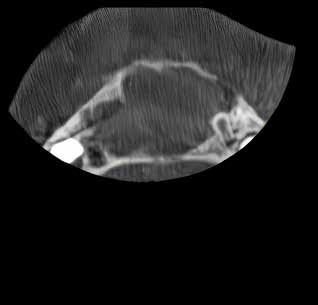

Patienttilfælde 1 (Fig. 1) er en 37-årig kvinde, henvist efter succesfuld behandling af stadie 3-parodontitis. Der er nu sundt

Før behandling

parodontium, ingen pocher over 4 mm, og både blødnings- og plakindeks er under 10 %. Patienten er motiveret for ortodontisk behandling, da hendes tænder er vandret over tid, delvist som følge af reduceret parodontium.

Der ses anterior trangstilling i begge kæber og overerupterede 1+1 og 2,1-1,2, hvilket resulterer i dybt bid med 2- tæt på ganepåbidning. Der er normale sidetandsrelationer, men der ses 5 mm horisontalt overbid (HOB) og 7 mm vertikalt

overbid (VOB). Papillen mellem 1+1 er betydeligt reduceret pga. fæstetab, og de mesialt kippede 1+1 har resulteret i en ”dark triangle”. Den facioorale funktion er for nuværende i.a. Panoramarøntgen (Fig. 1, I) viser marginalt knogletab i begge kæber og fravær af 8,7+7,8 og 8,7-8.

Objektivt anbefales behandling af det dybe bid, som ubehandlet forventes at forværres yderligere over tid. Patienten har ønske om behandling med æstetisk ortodontisk apparatur, alignere, og det vurderes muligt at behandle malokklusionen med alignere. Dog anbefales det generelt, at alignere undgås eller benyttes med væsentlige modifikationer af alignerens retention ved tandmobilitet, da dette ellers kan medføre jiggling, når aligneren tages af og på mange gange dagligt. På den anden side er der nogen evidens for, at alignerbehandling er associeret med bedre renhold og parodontal sundhed sammenlignet med fast apparatur (16).